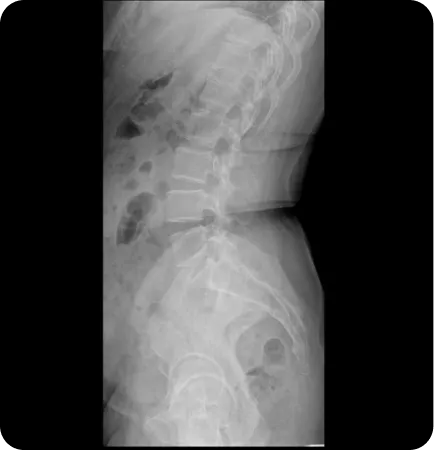

Pattern 01.

회전성 부정렬

골반이 앞뒤로 회전한 상태 (80~85%)

Ant.tilt (AS)

Post.tilt (PI)

Pattern 02.

골반 플레어 좁아진 골반과 벌어진 골반

골반 앞쪽이 벌어지거나 모인 상태 (40~50%)

Inflare (EX)

Outflare (IN)

Pattern 03.

업 슬립 골반 높이 차이

한 쪽 골반이 위로 올라간 상태 (15~20%)

Upsilp

Downslip

골반 틀어짐을 패턴을

알고 교정하니까

골반은 요추와 고관절을 연결하는 중심일 뿐 아니라 천골과 장골 등 6개의 관절면이 맞닿아 있는 복잡한 구조물이기 때문에 교정이 어렵습니다. 하지만 당당의 오랜 골반교정 노하우로 골반 틀어짐이 자주 생기는 패턴 4가지와 변이 6가지로 이루어진 총 10가지 패턴으로 구분하여 신속하고 정확한 치료를 합니다.